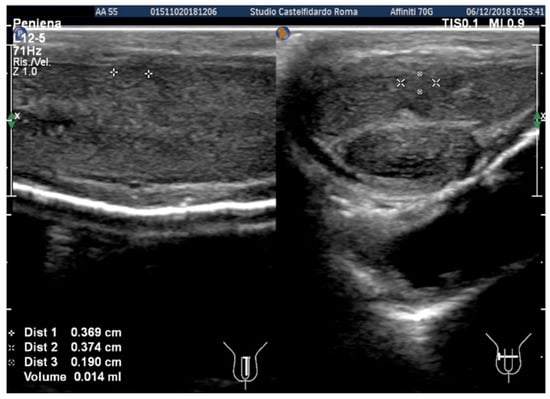

| 3 | 30 years | Left varicocele | Proximal third | (A) 12.2 × 11.2 × 2.81 mm volume = 203 mm3 (B) No plaque detected | (A) No penile deformation (B) No penile deformation | VAS score = 5 Pain disappeared after 4 months | 26 > 26 | 4 months | Orally: propolis 600 mg + bilberry 160 mg + silymarin 400 mg + ginkgo biloba 250 mg + vitamin E 800 IU/daily for 4 months + topically: diclofenac gel 4%/2× daily for 4 months Note: Penile injections not needed |